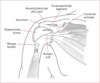

Borders and contents of quadrangular space

- Borders: humerus, triceps long head, teres minor, teres major

- Contents: Axillary nerve and posterior humeral circumflex artery

Borders and contents of triangular interval

- borders: humerus, triceps long head, teres major

- contents: radial nerve profunda brachii artery

Borders and contents of triangular space

- borders: teres minor, teres major, long head of tricpes (lateral)

- contents: scapular circumflex artery